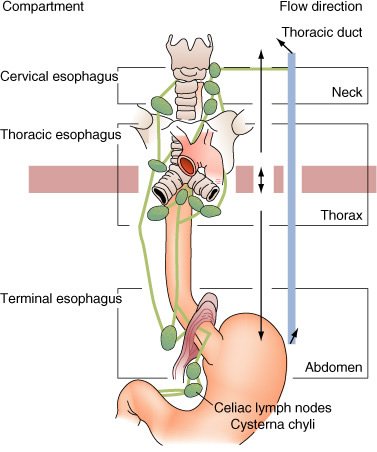

Mapa de linfonodos para câncer esofágico. A, Visão anterior. B, Visão lateral esquerda. C, Visão lateral direita. Estações ganglionares: l, supraclavicular; 2R, paratraqueal direito; 2L, paratraqueal esquerdo; 3P, mediastinal posterior; 4R, ângulo traqueobrônquico direito; 4L, traqueobrônquico esquerdo; 5, aortopulmonar; 6, mediastinal anterior; 7, subcarinal; 8M, paraesofagiano médio; 8L, paraesofagiano inferior; 9, ligamento pulmonar inferior; 10, hilar; 15, diafragmático; 16, paracardial; 17, gástrico esquerdo; 18, hepático comum; 19, esplénico; 20, celíaco A falta de serosa do esôfago tende a favorecer a extensão local do tumor.

A extensa drenagem linfática mediastinal, que se comunica com os vasos colaterais cervicais e abdominais, é responsável pelo achado de metástases ganglionar, mediastinal, supraclavicular ou do tronco celíaco em, pelo menos, 75% dos pacientes com carcinoma esofágico. Cânceres do esôfago cervical drenam para os linfonodos cervicais profundos, paraesofágicos, mediastinais posteriores e traqueobrônquicos. Os tumores do terço inferior disseminam para os linfonodos paraesofagianos, celíacos e do hilo esplénico. A disseminação a distância para fígado e pulmões é comum.